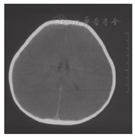

患儿,男,2岁5个月时因"间断呕吐、腹泻、昏迷及嗜睡1年余"就诊。患儿1岁3个月内发育正常,1岁3个月时进食大量甜瓜,1 d后呕吐、腹泻、腹痛,当地医院考虑肠套叠,经气灌肠治疗后好转。平素厌食水果及甜食,自述吃水果后腹痛,喜欢肉类、蛋、粮食。患儿1岁3个月~2岁1个月间断呕吐发作4次,伴腹泻、嗜睡、昏迷及肝损害,进食水果后或患上呼吸道感染时发作,伴酸中毒,血pH低至6.9,未检测血糖,每次发作时经葡萄糖、碳酸氢钠等静脉输注后病情很快缓解。外院血氨基酸、酯酰肉碱谱及尿有机酸分析结果大致正常。发作间期无异常。患儿于2岁5个月时进食较多水果,30 min后出现呕吐,昏迷,抽搐。当地医院检测发现低血糖(0.52~2.30 mmol/L,正常参考值3.61~6.11 mmol/L),代谢性酸中毒,血乳酸增高(2.2~15.9 mmol/L,正常参考值0.5~2.0 mmol/L)。尿酮体阳性,尿蛋白微量。血清电解质正常,丙氨酸转氨酶(ALT)增高(78~123 IU/L,正常参考值0~40 IU/L),天冬氨酸氨基转移酶(AST)增高(94~154 IU/L,正常参考值0~45 IU/L)。头颅CT、磁共振成像(MRI)显示弥散性脑水肿、尾状核、苍白球及壳核肿胀(图1、图2),可见广泛血管炎性水肿及细胞毒性水肿,符合低血糖脑病。静脉滴注葡萄糖、碳酸氢钠、甘露醇及保肝药物后一般情况好转,但此后睡眠中时有抽搐,为局灶性发作,四肢肌张力增高,伴痉挛型瘫痪。

饮食治疗原则为限制果糖摄入,避免食用水果、奶类、南瓜、动物肝脏及胡萝卜,鼓励肉、蛋、豆类、鱼虾、粮食及菜类等食物,避免长时间饥饿。为缓解肌紧张,口服盐酸苯海索片及氯硝西泮。为保证营养,给予左卡尼汀、维生素B12、A、D等支持治疗。治疗后1个月后复查脑MRI显示侧脑室扩张,提示脑萎缩(图4)。随访至3岁,智力逐渐恢复,痉挛型截瘫逐渐好转,治疗后未再出现呕吐、腹痛及抽搐等症状。